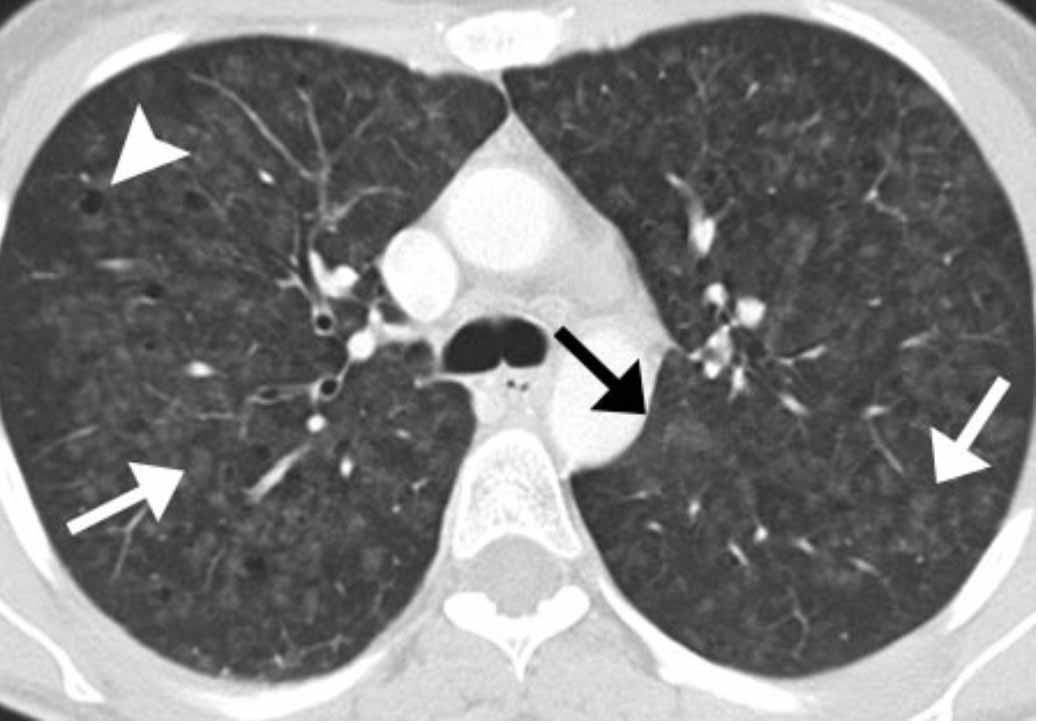

Ковид ассоциированный

Ковид ассоциированный 114 фотографий